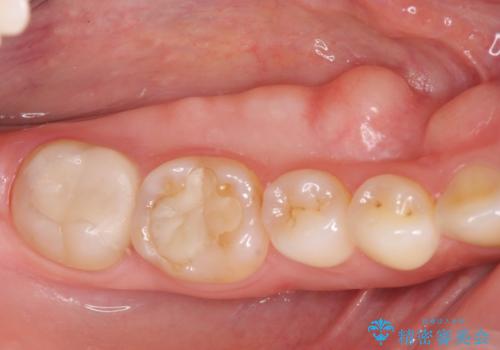

発音の邪魔となる骨隆起の除去

- 徐々に大きくなってきた骨隆起の除去を希望され来院されました。

下顎隆起を切除することで舌を収めるスペースを確保し発音のしやすさの向上を図ります。